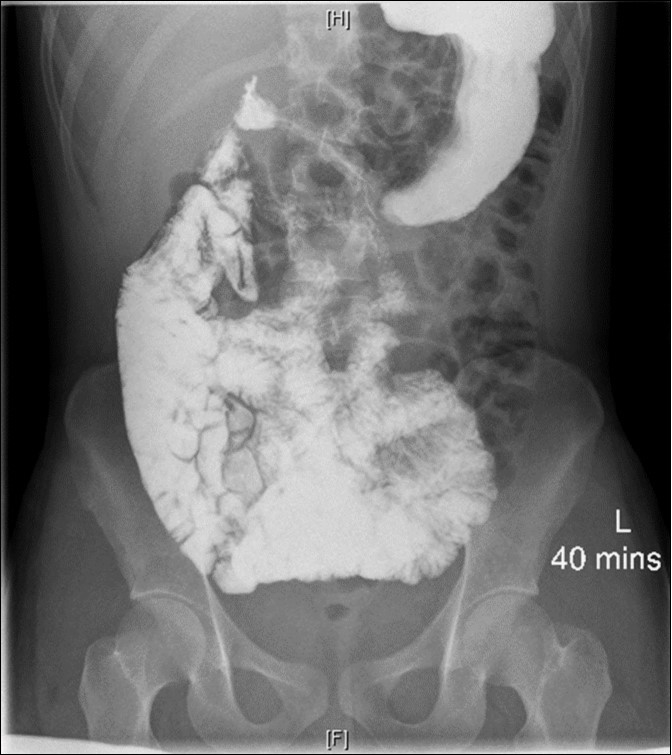

As part of the workup, an enterography magnetic resonance imaging (MRI) was done and showed non-rotation with the small bowel and colon in the right and left abdomen, respectively (Figure 1). A complementary upper gastrointestinal series (UGIS) was requested and the duodenal jejunal junction was abnormally located confirming malrotation (Figure 2).

Figure 2.UGIS showing malrotation

The diagnosis is usually pointed out in radiologic studies. The absence of the colon on the right lower quadrant can suggest the diagnosis, however plain radiographs are not sensitive nor specific for the diagnosis of malrotation. Inversion of the SMV/SMA can be found on ultrasound but these have not been proven to be superior to an UGIS1. UGIS is still considered to be the gold standard for the diagnosis of malrotation. In our case, MRI suggested a non-rotation that was later proven to be malrotation on UGIS and confirmed by intraoperative findings. A retrospective study that included 145 patients who underwent UGIS and MRI showed a sensitivity of 100% and specificity of 92% for abnormal rotation when read by a pediatric radiologist8.